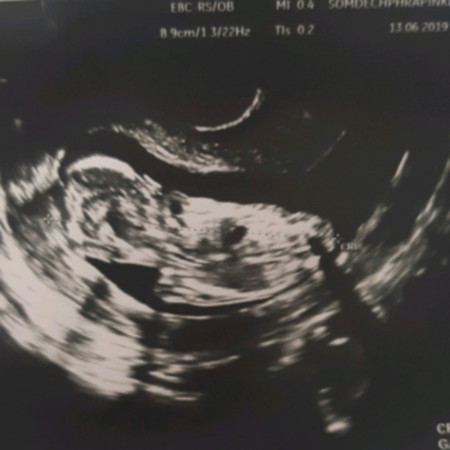

น้องนอนหันหลังใช่ไหมคะไม่เหนแขนขาน้องเรย ดูยังไม่ค่อยเก่ง ซาวนด์ 14สัปดา

น่าจะเป็นตอนที่มือกับเท้างอพอดีนะคะ